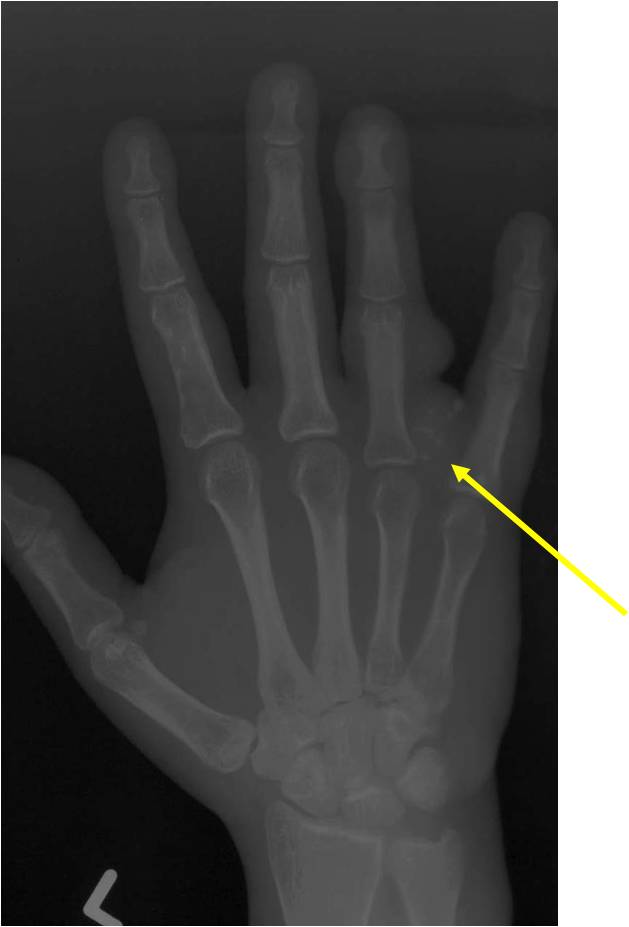

Maffucci Syndrome

- (Described in 1881 by Maffucci as enchondromatosis with hemangiomas)

Clinical Data:

- Very rare; Nonhereditary

- Multiple Enchondromas

- Cavernous Hemangiomas anywhere in skin and subcutaneous tissues of body

- May be unilateral or bilateral, may be only a few or many

- Phleboliths (calcifications) usually seen in hemangiomas on X-ray

- Mild male predilection

- Hands and feet greatest involvement

Imaging characteristics:

- Lesions seen in infancy

- Typical enchondromas

- Geographic IA-IIB with expansion

- Lytic columns from epiphyseal plate

- Chondroid matrix calcification

- Growth disturbance and bowing

- Enchondroma growth slows after growth plate closure

- Maffucci: Soft tissue mass/hemangiomas with phleboliths